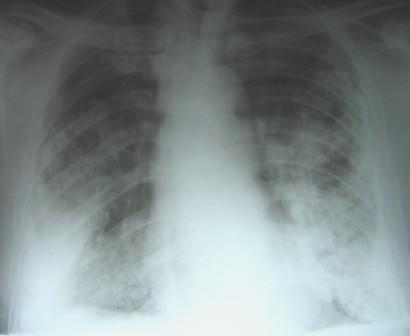

A 62-year-old man, retired shipping company employee, who was to undergo resection of a vocal cord nodule, was referred to the Chest clinic for preoperative evaluation for an abnormal chest radiograph (Figure 1).

Figure 1: Chest radiograph on presentation showing bilateral interstitial shadows, pleural plaques and diffuse pleural thickening.

On chest radiography, pleural plaques when calcified and bilateral (as in this case) are the most common indicators of inhalation, retention and biologic effect of asbestos fibers [2].